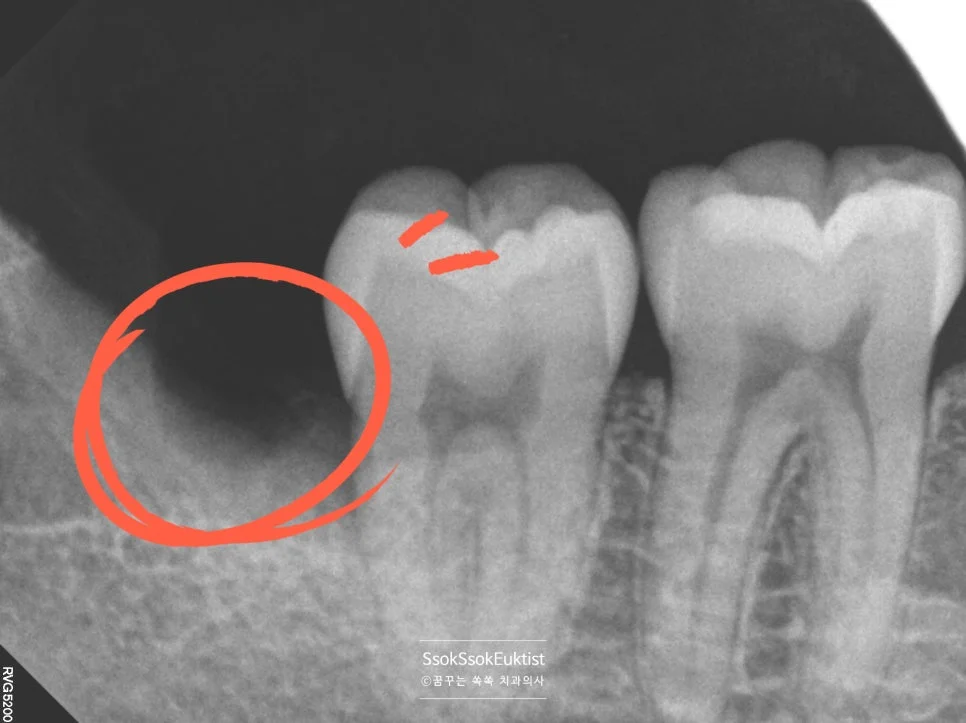

2. 한편 통증이 없더라도 매복 사랑니는 언젠가는 바로 앞어금니에 충치를 만들고, 잇몸뼈까지 잃게 합니다.

이렇게 사랑니 때문에 생긴 바로 앞 제2대구치의 충치는 치료가 매우 어렵고, 그로 인해 어금니를 뽑아야 하는 상황이 올 수 있습니다.

Q. 통증이 없는 매복 사랑니도 반드시 빼야 하나요?

매복 사랑니는 당장 아프지 않아도 바로 앞 어금니(제2대구치)에 충치를 만들거나 잇몸뼈를 소실시키는 원인이 됩니다. 앞어금니를 잃게 되면 임플란트까지 필요할 수 있으므로, 증상이 없더라도 예방적 발치를 권유 드립니다. 단, 위아래 사랑니가 모두 바르게 맹출하여 서로 교합하고 충치나 잇몸 질환이 없다면 발치하지 않아도 됩니다.